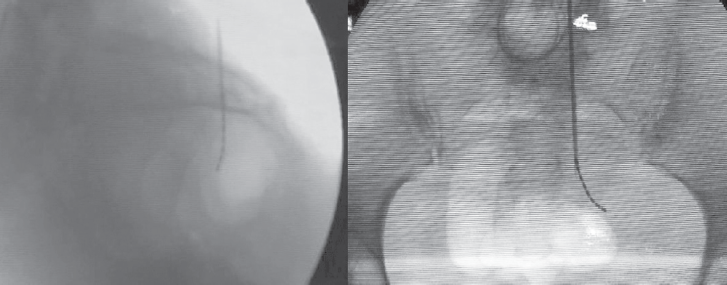

The third sacral foramen (S3) was marked according to the generally accepted method under radiological control [8]. As a rule, it is projected onto the skin at the intersection of the vertical line drawn through the medial edges of the sacral foramen with the horizontal line drawn along the lower edge of the sacroiliac joint (Fig. 1).

Fig. 1. The X-ray of the pelvic bones in a direct projection indicating anatomical landmarks and conditional lines drawn through them to determine the hole of the S3, the arrow indicates the edge of the ileosacral joint, the circle on the S3 indicates the hole (left). On the right the a projection of the third sacral hole is visualized

Рис. 1. Рентгенограмма костей таза в прямой проекции с указанием анатомических ориентиров и проведенных через них условных линий для определения отверстия S3, стрелкой указан край илиосакрального сочленения, кругом S3 обозначено отверстие (слева). Справа на снимке металлическим инструментом указаны проекции третьего сакрального отверстия